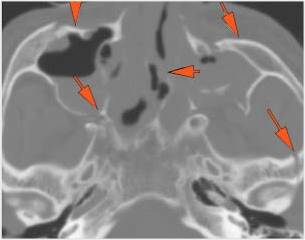

Orbits and Orbital Zygomatic Complex

There is evidence of a subperiosteal hematoma along the medial or lateral wall, roof or floor of the orbit.

The circumferential extraconal and the intraconal orbital fat are infiltrated.

The extraocular muscles are swollen, infiltrated or herniated into a fracture site.

There is evidence of bony injury along the walls and/or floor of the orbit.

The mesial naso-orbito-ethmoid complex is fractured. Specifically, there is bony injury of the nasal bones or the frontal process of the maxilla and the medial walls of the orbit are abnormal.